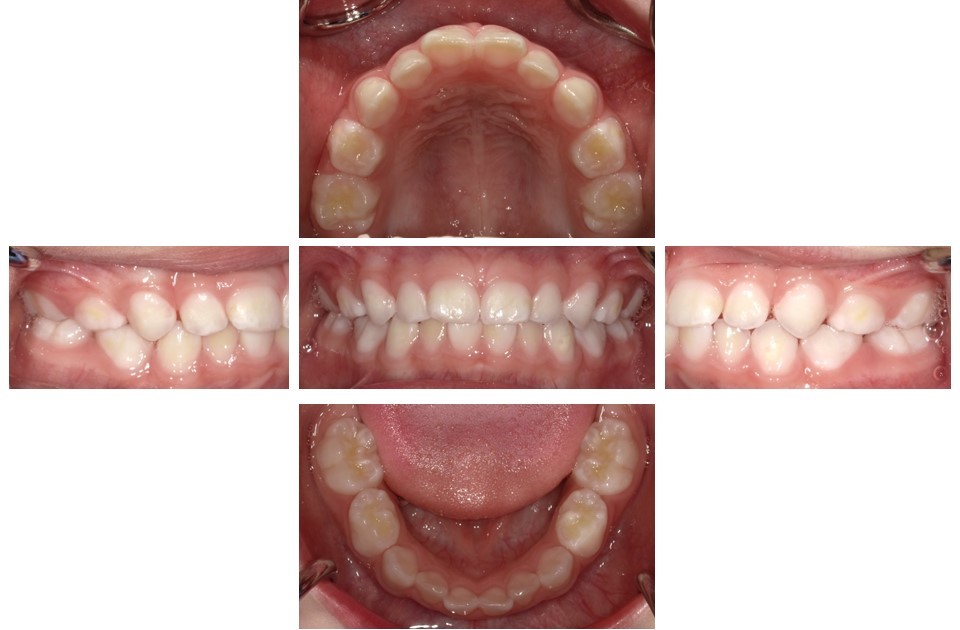

子どものう蝕の数は年々減少しており、う蝕の全くない子どもが多くいますが(図2)、重度のう蝕を有する子どもが一定程度存在し続けています(図3)。3歳まではう蝕がないことが一般的であり、この頃までに既にう蝕がある子どもに対しては、将来的にう蝕リスクが高い対象として、特に配慮していく必要があります。子どものう蝕の発生に影響する要因として口腔清掃不良が挙げられますが、砂糖の摂取に関連した不適切な生活習慣にも注目する必要があります。う蝕になりやすいのは、ほとんど唾液が分泌されず自浄作用が低下する「就寝時」です。そこで、就寝前に適切な口腔清掃を行うことが重要であり、砂糖を含む食品の摂取を控えるように指導してください。

(図2)う蝕のない小児(3歳0か月男児)